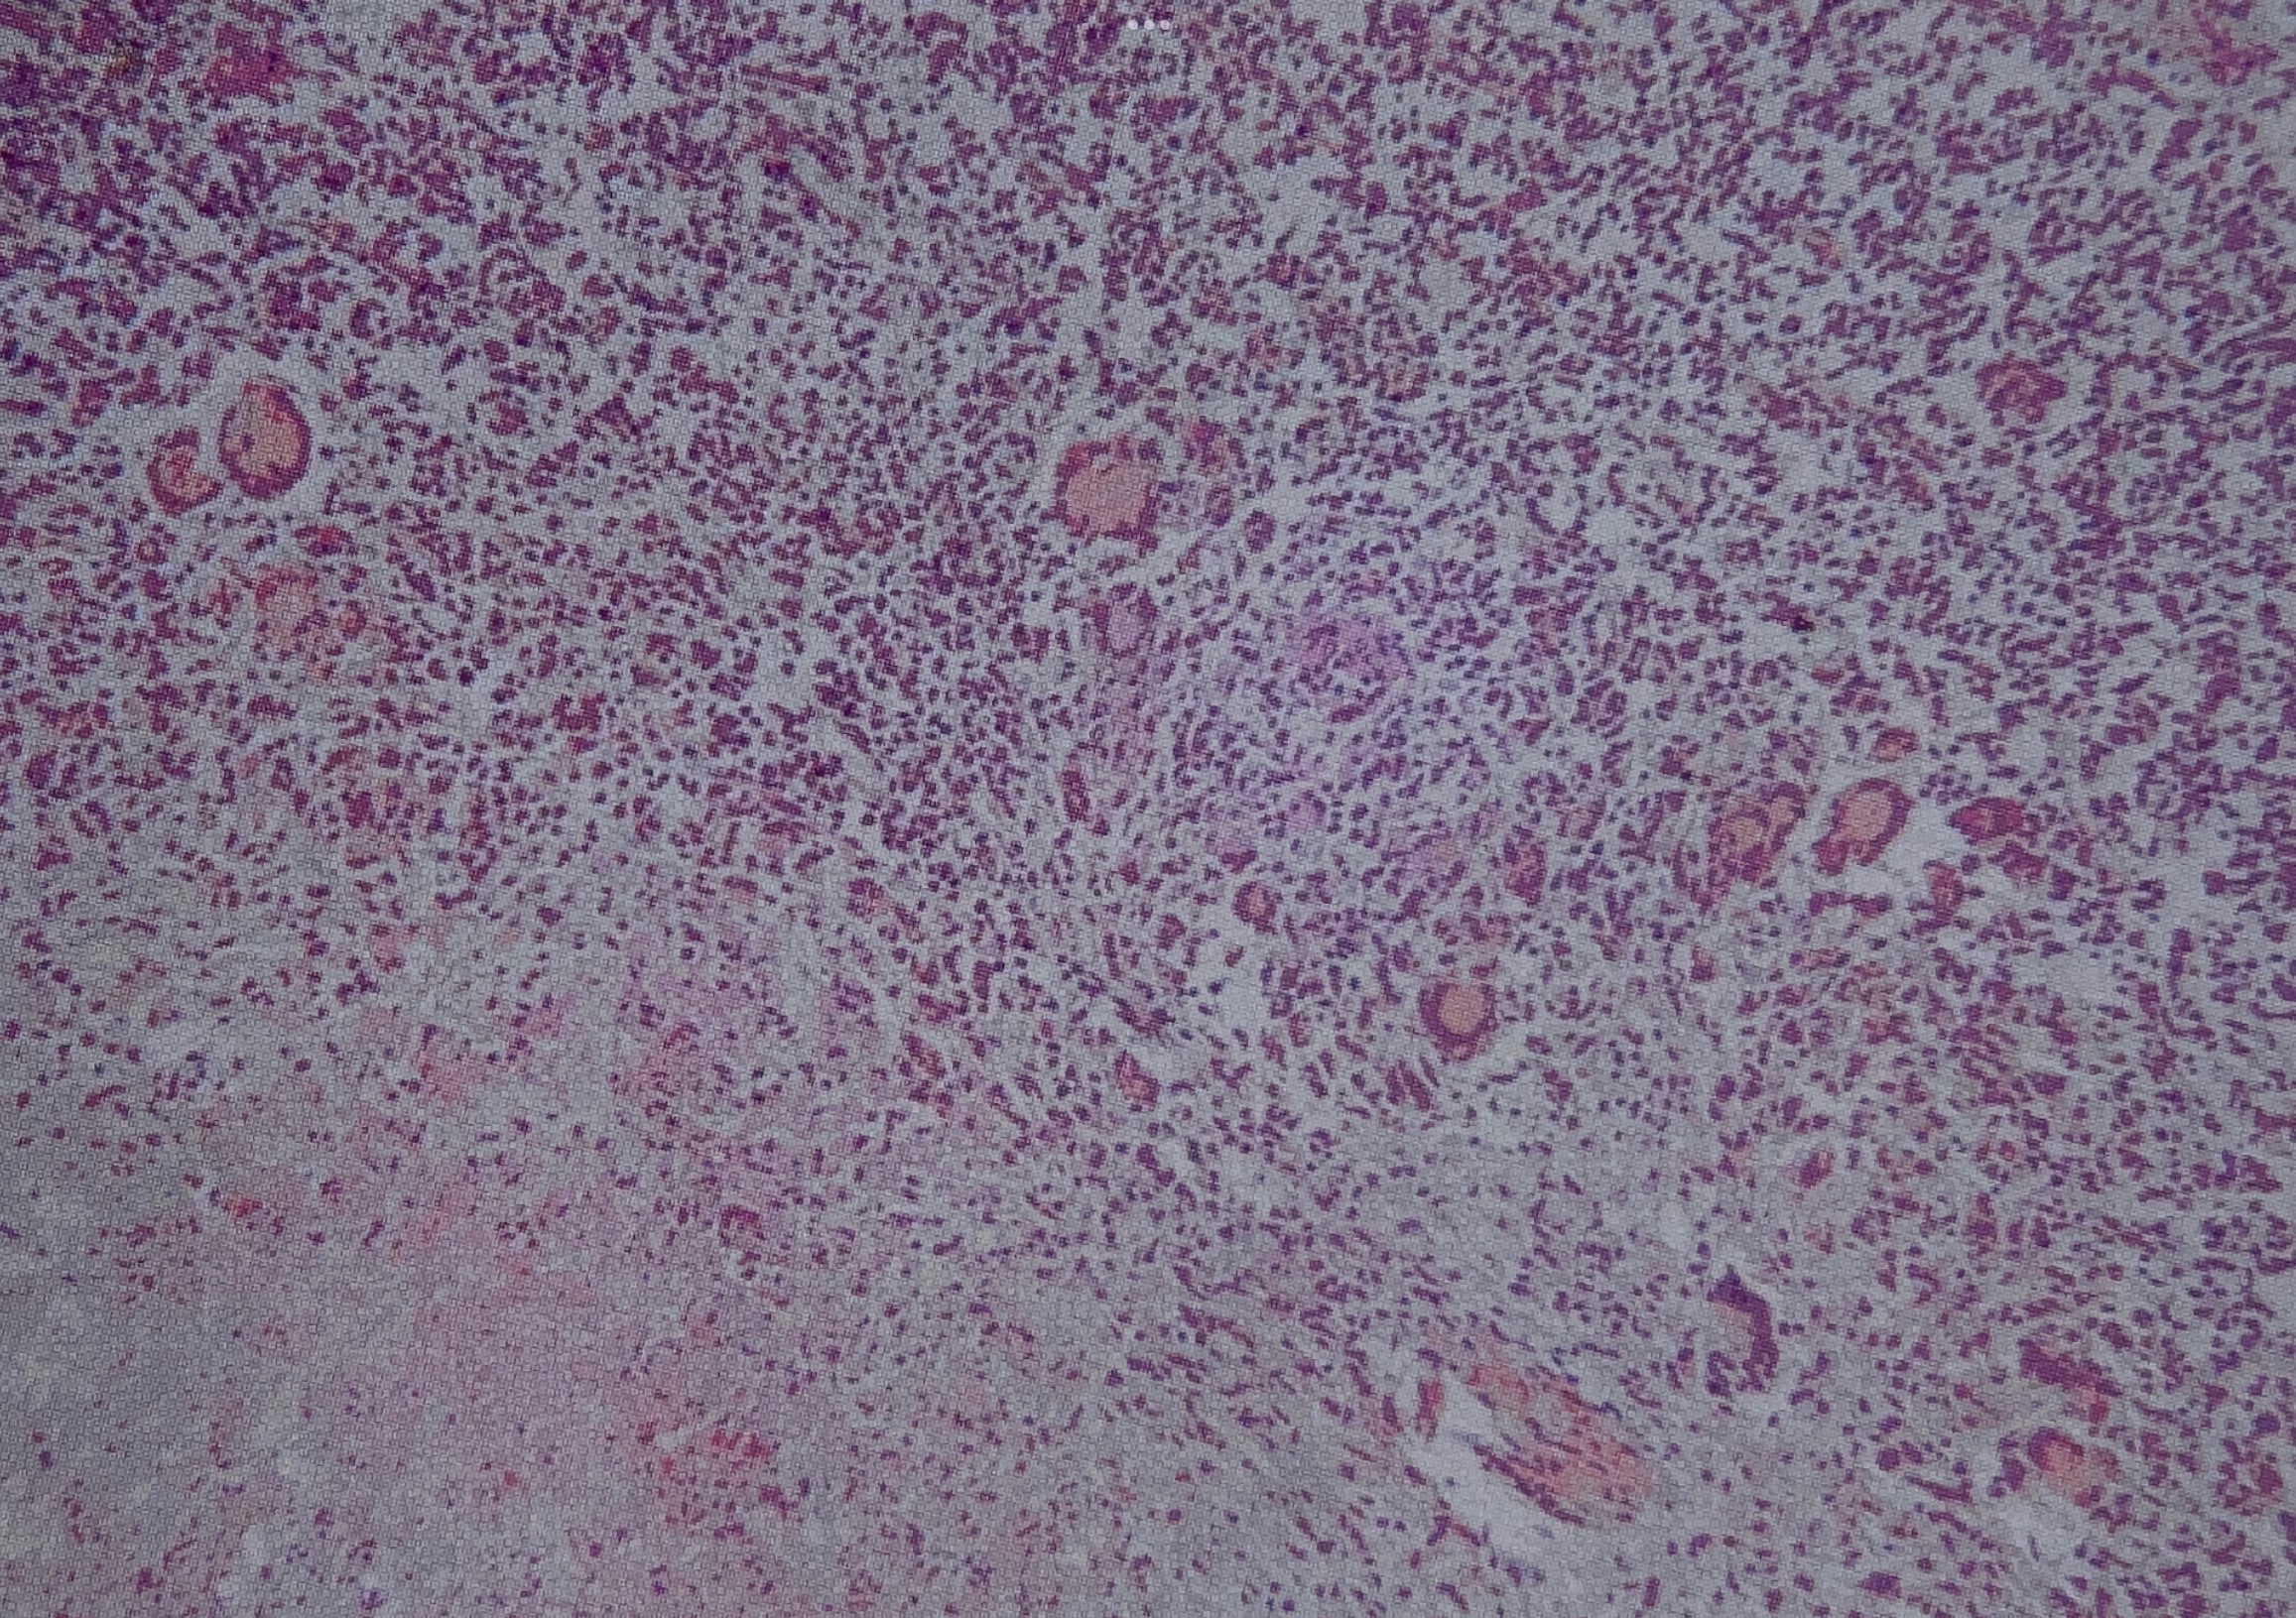

显微镜下人类粟粒结核活检片

图片尺寸1200x801

粟粒性肺结核

39#粟粒型肺结核